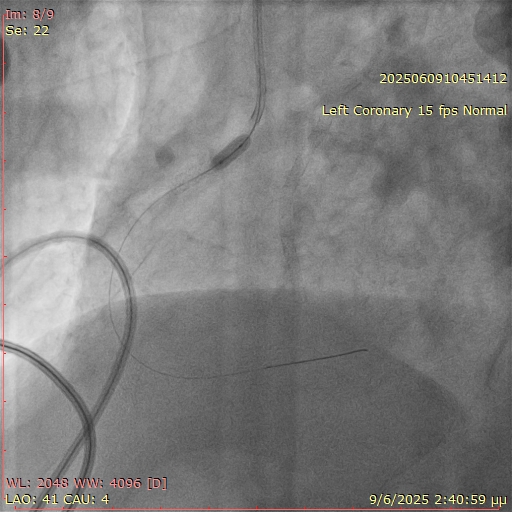

Unexpected resistance was encountered while attempting to deliver balloons across the ostial segment (Figure 2). Suspecting an underlying issue, the angiographic projection was modified to a more cranial view. This revealed that a significant portion of the prior stent was protruding into the aorta, obstructing device passage (Figure 3).